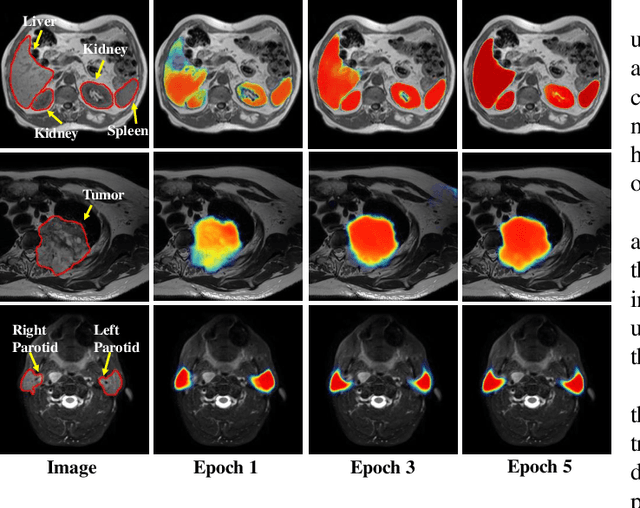

Abstract:We developed a new joint probabilistic segmentation and image distribution matching generative adversarial network (PSIGAN) for unsupervised domain adaptation (UDA) and multi-organ segmentation from magnetic resonance (MRI) images. Our UDA approach models the co-dependency between images and their segmentation as a joint probability distribution using a new structure discriminator. The structure discriminator computes structure of interest focused adversarial loss by combining the generated pseudo MRI with probabilistic segmentations produced by a simultaneously trained segmentation sub-network. The segmentation sub-network is trained using the pseudo MRI produced by the generator sub-network. This leads to a cyclical optimization of both the generator and segmentation sub-networks that are jointly trained as part of an end-to-end network. Extensive experiments and comparisons against multiple state-of-the-art methods were done on four different MRI sequences totalling 257 scans for generating multi-organ and tumor segmentation. The experiments included, (a) 20 T1-weighted (T1w) in-phase mdixon and (b) 20 T2-weighted (T2w) abdominal MRI for segmenting liver, spleen, left and right kidneys, (c) 162 T2-weighted fat suppressed head and neck MRI (T2wFS) for parotid gland segmentation, and (d) 75 T2w MRI for lung tumor segmentation. Our method achieved an overall average DSC of 0.87 on T1w and 0.90 on T2w for the abdominal organs, 0.82 on T2wFS for the parotid glands, and 0.77 on T2w MRI for lung tumors.